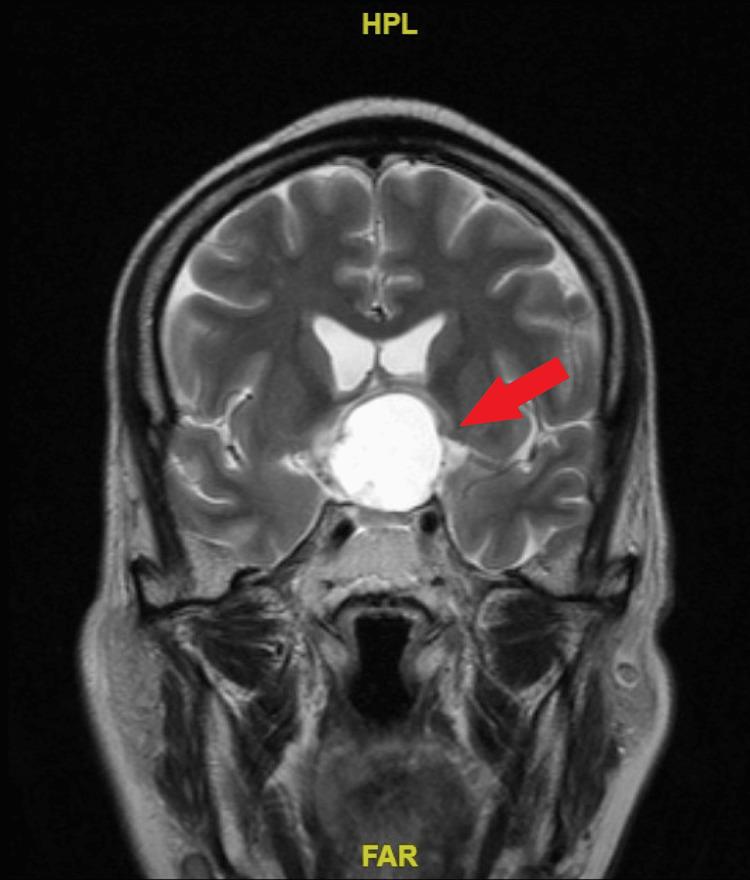

The afferent visual system is one of the most common structures involved in patients with craniopharyngioma, and the manifestations include deficits in visual acuity, color vision, and visual fields. Here, we report a case of craniopharyngioma that presented with acute blindness in an elderly man. A healthy 54-year-old man presented with an acute progressive blurring of vision and became blind in six weeks. He developed symptoms of increased intracranial pressure only a week after becoming blind. On examination, visual acuity in both eyes was no perception of light (NPL). He also had left esotropia with restriction of left eye abduction. Both pupils were not responsive to light. The anterior segment was normal in both eyes. Fundoscopy showed bilateral pale optic discs. Computed tomography scan and magnetic resonance imaging revealed a suprasellar mass consistent with craniopharyngioma that compressed the optic chiasma and adjacent brain structures with the presence of hydrocephalus. He underwent uneventful tumor debulking surgery. However, his vision remained NPL postoperatively. Ocular manifestations could be the only symptoms in craniopharyngioma. The delayed presentation may lead to a guarded prognosis.